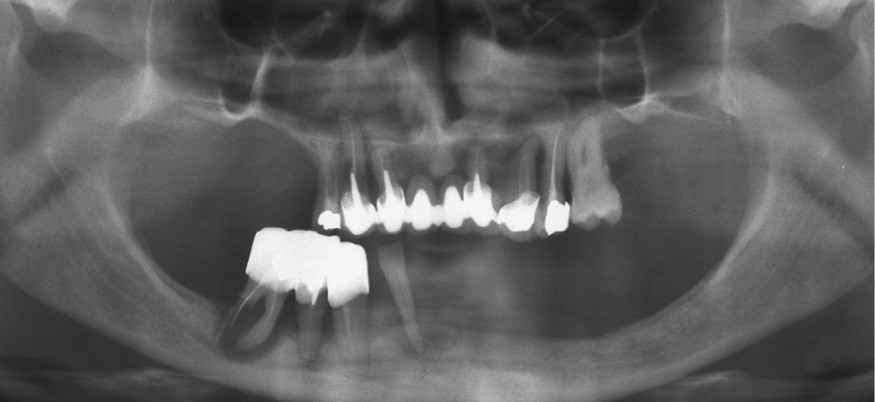

Il s’agit d’une patiente de 64 ans n’ayant pas d’antécédent particulier, qui est prise en charge dans le service de chirurgie maxillo-faciale du CHU de Nantes pour une situation dentaire préterminale au niveau maxillaire et mandibulaire (fig. 1).